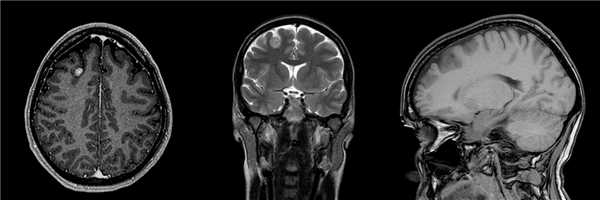

Пациентка 37 лет при плановом обследовании 1 год назад выполнена МРТ головного мозга, выявившая опухоль правой лобной доли (асимптомную).

![]()

Проведена операция - радикальное удаление опухоли. Для минимизации размеров кожного разреза и трепанационного окна, операция проводилась с использованием нейронавигационной системы. Результат гистологического исследования - ганглиоглиома.

Пациентка выписана на 4 сутки после операции без неврологического дефицита.Глиома головного мозга